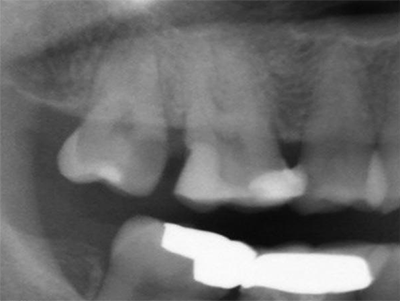

术前X-ray局部放大图

检查:17 MO龋损,叩:(-),探:(+),冷测持续疼痛,牙周无红肿。X-ray示:龋损近髓腔,根尖无阴影。